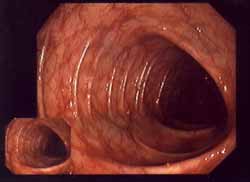

Das

einen grossen Teil der Substanz verloren Das Alzheimerhirn hat gegenüber dem normalen Hirn einen grossen Teil der Substanz verloren. Quecksilber ist wesentlich daran beteiligt.

Die Alzheimer-Krankheit wurde erstmals 1907 vom Breslauer Neurologen Alois Alzheimer beschrieben und tritt bevorzugt bei Frauen zwischen dem 55. und 65. Lebensjahr auf.

Für die überwiegende Zahl aller Fälle eines geistigen Abbaus (Demenz, Einschränkung bzw. Verlust aller Denkprozesse) ist derzeit die Alzheimer-Krankheit verantwortlich. Durchschnittlich tritt der Tod nach 10 Jahren ein (S.41).

Die Ursache ist nach schulmedizinischer Meinung unbekannt; eine früher als Auslöser betrachtete Aluminiumbelastung spielt jedoch eher als Co-Faktor eine Rolle. Etwa 5 % der Alzheimer-Fälle sind genetisch bedingt (Mutationen auf Chromosom 14, 19, 21). Bei der Krankheit lagern sich krankhafte Proteine im Gehirn ab (senile Plaque durch Beta-Amyloid) (S.41).

[Gehirnuntersuchungen zeigen Quecksilber als Faktor auf]

Einige neuere Studien legen den Zusammenhang zwischen langjähriger Quecksilberbelastung und Alzheimer-Erkrankung nahe.

Die wichtigste therapeutische Massnahme wäre die Vorbeugung dieser schweren Erkrankung. Es würde sich auch volkswirtschaftlich lohnen, Amalgam zu verbieten, um die Alzheimer-Erkrankung zu vermeiden. Die Krankheit kostet das Gesundheitssystem viel Geld und wird in den nächsten Jahren stark zunehmen (S.42).

Untersuchung der Gehirne von Verstorbenen auf Spurenelemente

Verglichen wurden zwei Gruppen. Die eine fasste Menschen zusammen, die an Alzheimer gestorben waren, in der anderen befanden sich alle anderen Patienten. Der Quecksilberspiegel war im Gehirngewebe der Alzheimerpatienten erhöht, und zwar bis zum Vierfachen in Hirnregionen, die bei der Alzheimer-Krankheit degenerieren (S.41).